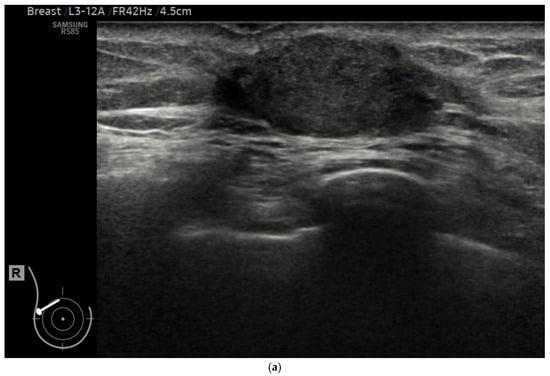

2.4. AI Analysis